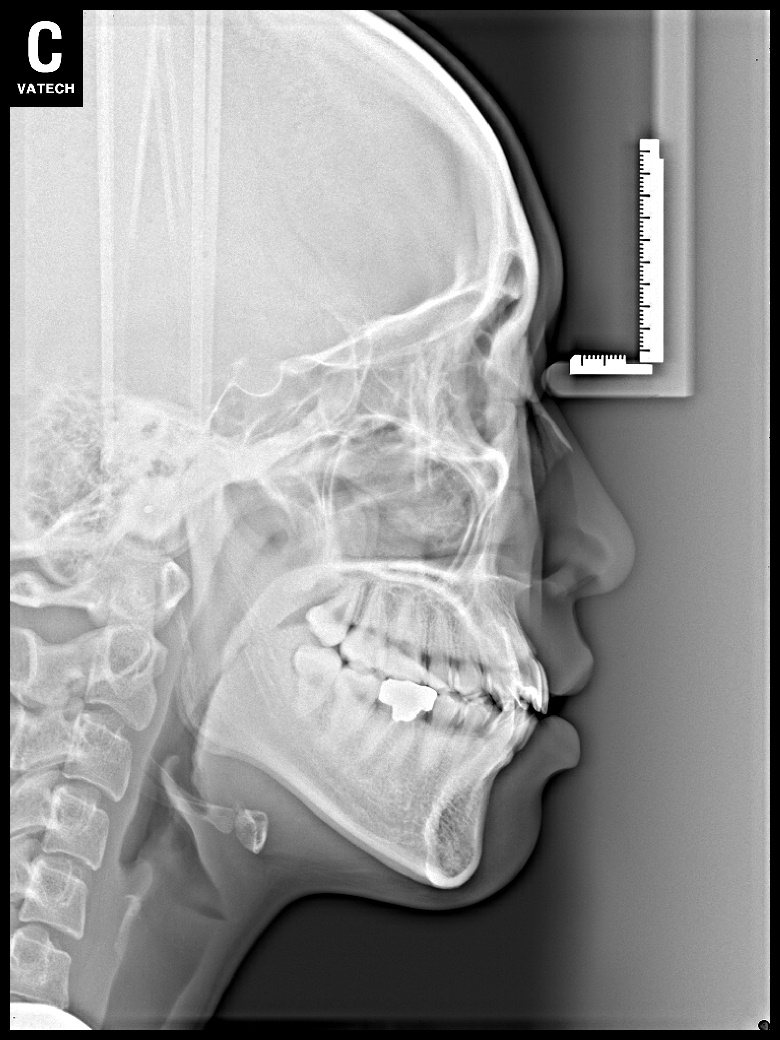

치료 후 사진입니다.